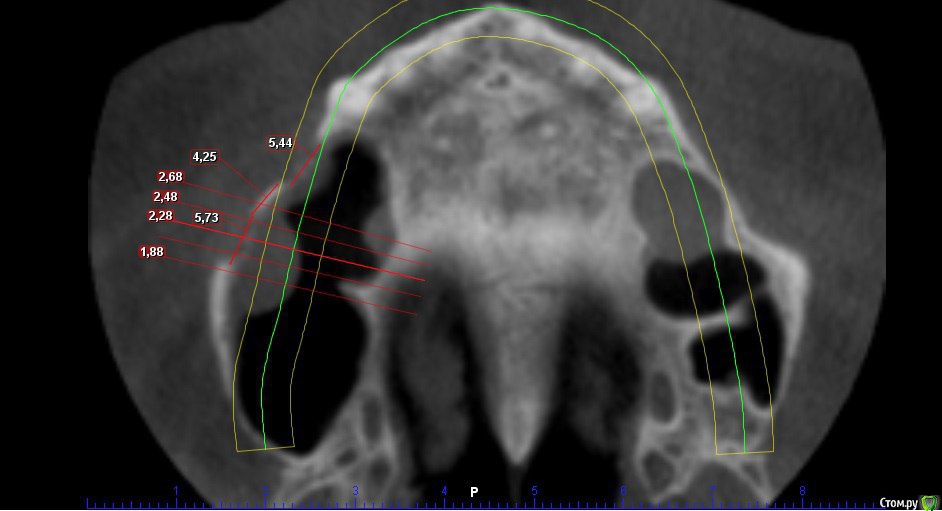

Kovalov Igor Опубликовано 19 мая, 2016 Поделиться Опубликовано 19 мая, 2016 (изменено) Здравствуйте уважаемые форумчане! Нужен совет по повторному синуслифтингу....3 месяца назад проводилась попытка синуслифтинга в 1 сегменте, отсутствие 14,15,16 зубов ... Разрез, формирование окна, в этом случае выбрал вход в синус с двух окон в проекции 14 и 16, получить перфу возле септы в области 16 когда отслаивал ... 14 отслойка без проблем... закрыл окна мембраной и ушил отправил погулять на 2,5-3 месяца.Вопрос как поступить ? Сделать одно большое окно? Как быть со спайками и как сложно их отделять ? Мембрану под перфу не подложил так как не делал ниразу этого... Кт после 3х месяцев ... Изменено 19 мая, 2016 пользователем Kovalov Igor Ссылка на комментарий

red_butler Опубликовано 21 мая, 2016 Поделиться Опубликовано 21 мая, 2016 Куда вы 2гр L сыпите та? Тромбуете штоль?Даже еще раз пересмотрел срезы, Вы считаете что на такой операционной площади и при таком строении синуса расход будет меньше? 3 Ссылка на комментарий

Kovalov Igor Опубликовано 21 мая, 2016 Автор Поделиться Опубликовано 21 мая, 2016 Даже еще раз пересмотрел срезы, Вы считаете что на такой операционной площади и при таком строении синуса расход будет меньше?Ушло 2 грамма вы правы! ))) Спасибо всем за советы , ошибки были в первом случае малое и высоко расположенное окно, сделал в этот раз одно большое окно, спайки были только по периметру окна , было ощущение что окно начало заростать костью через три месяца, будто пластинка была поверх мембраны , может показалось ...Отслаивал до септы, графт 1,5 гр. в синус и 0,5 латерально от винтов и укрыл мембраной 25*25 владмива, мембрана не понравилась если честно ) Ссылка на комментарий